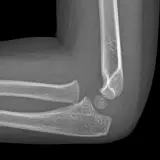

PACS์—์„œ ๊ธฐ๋Œ€ํ•  ์ˆ˜ ์žˆ๋Š” ๋ชจ๋“  ๋„๊ตฌ๋ฅผ ๊ฐ–์ถ˜ ์™„์ „ํ•œ ์ธํ„ฐ๋ž™ํ‹ฐ๋ธŒ ์ฆ๋ก€ — ์Šคํฌ๋กค, ์œˆ๋„์šฐ ์กฐ์ ˆ, ํ™•๋Œ€/์ถ•์†Œ, ํŒจ๋‹, ๊ณ„์ธก, ROI, ์ „์ฒด ํ™”๋ฉด ๋ชจ๋“œ๊นŒ์ง€ ์ง€์›ํ•ฉ๋‹ˆ๋‹ค.

์ฃผ์š” ์†Œ๊ฒฌ์„ ์ฆ๋ก€์— ์ง์ ‘ ํ‘œ์‹œํ•˜๋Š” ํ’๋ถ€ํ•œ ์ฃผ์„์ด ํฌํ•จ๋˜์–ด ์žˆ์Šต๋‹ˆ๋‹ค. ์ฆ๋ก€ ์„ค๋ช…์˜ ์—ฐ๊ฒฐ๋œ ์†Œ๊ฒฌ์„ ํด๋ฆญํ•˜๋ฉด ์Šค์บ” ๋‚ด ์ •ํ™•ํ•œ ์œ„์น˜๋กœ ๋ฐ”๋กœ ์ด๋™ํ•ฉ๋‹ˆ๋‹ค.